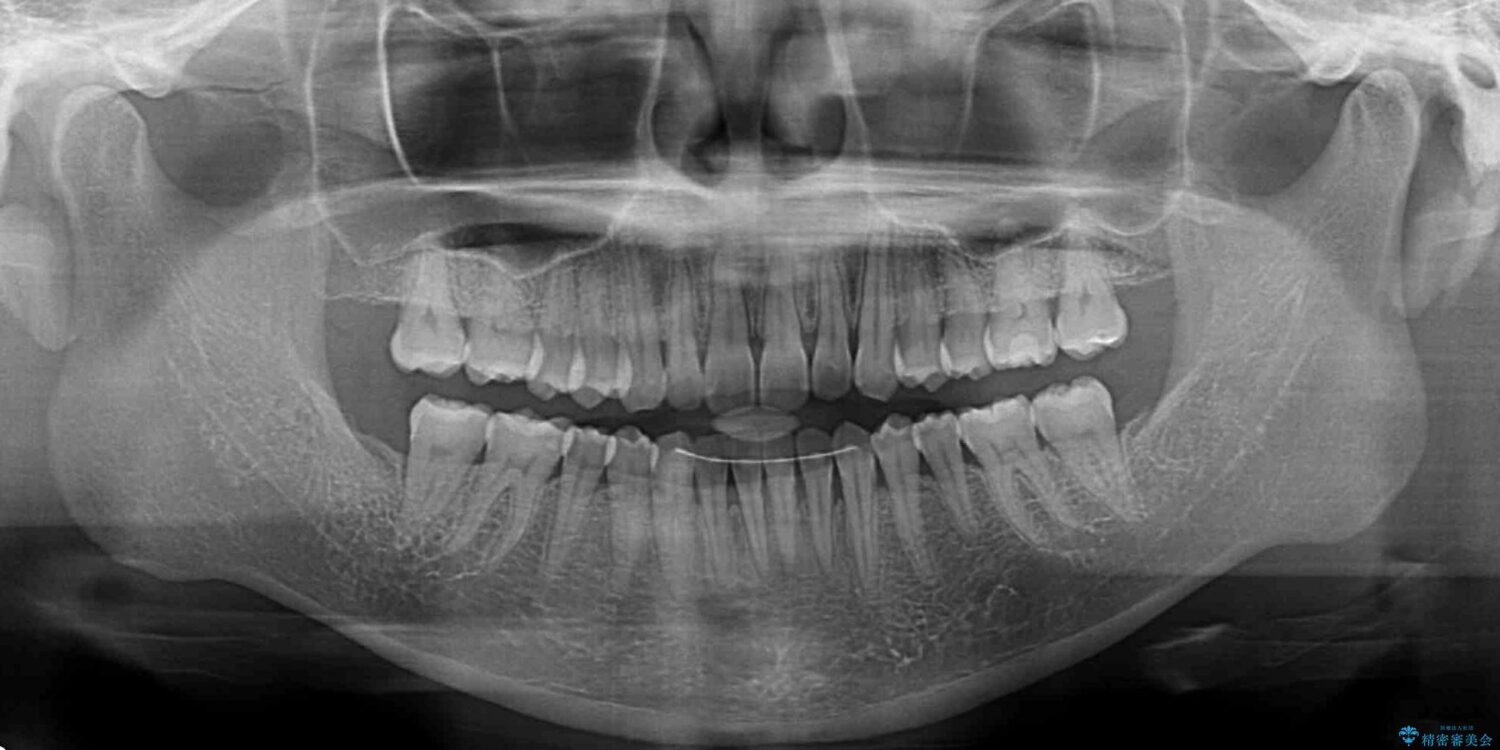

前歯のデコボコで前方に出ていることを気にして来院された患者様です。

上顎前歯が捻れて前方に飛び出しており、下顎前歯もそれに沿うようにデコボコとなっていました。

IPR(歯と歯の間を削る処置)によりスペースを獲得して上下顎前歯のデコボコを改善し、飛び出している前歯が引っ込むように設定し、インビザラインにて矯正治療を行うこととしました。

治療前

• 【モニター】前歯のデコボコをインビザラインで改善 治療前画像